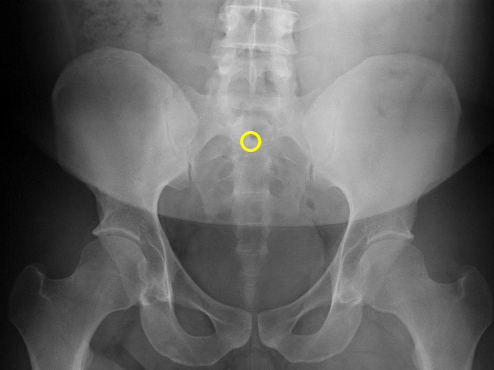

S2 tubercle

Pubic symphysis